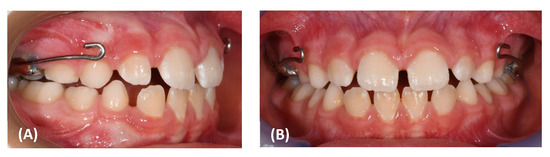

2. Materials and Methods

3. Results

| Overjet | 2.5 | 0.4 | 2.7 |

| Overbite | 2.5 | 1.1 | 3.6 |